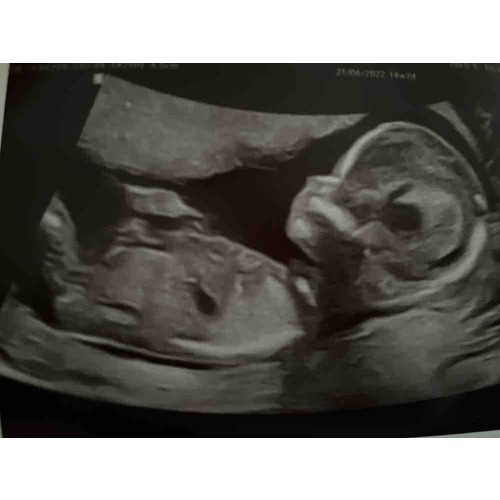

.. 13 weken echo gehad zooo benieuwd wat denken jullie jongen of meisje? Babybytes. Kun je met 13 weken echo het geslacht zien? Bij de 13 weken echo is het geslacht van je baby nog niet betrouwbaar te zien Zij weten alles van het medische stuk maar het geslacht vinden zij toch altijd spannend

Geslacht 13 weken echo? 1 24baby Forum. Voorbeelden van echo's op verwijzing zijn de termijn echo, de 13 weken echo, de 20 weken echo en echo's op medische indicatie zoals een groei-echo of een echo om de ligging van de placenta te beoordelen Tussen 14-16 weken van een zwangerschap kunnen de echoscopisten bij 3D Echo Barendrecht het geslacht van de baby zo goed zien dat er geen twijfel kan zijn